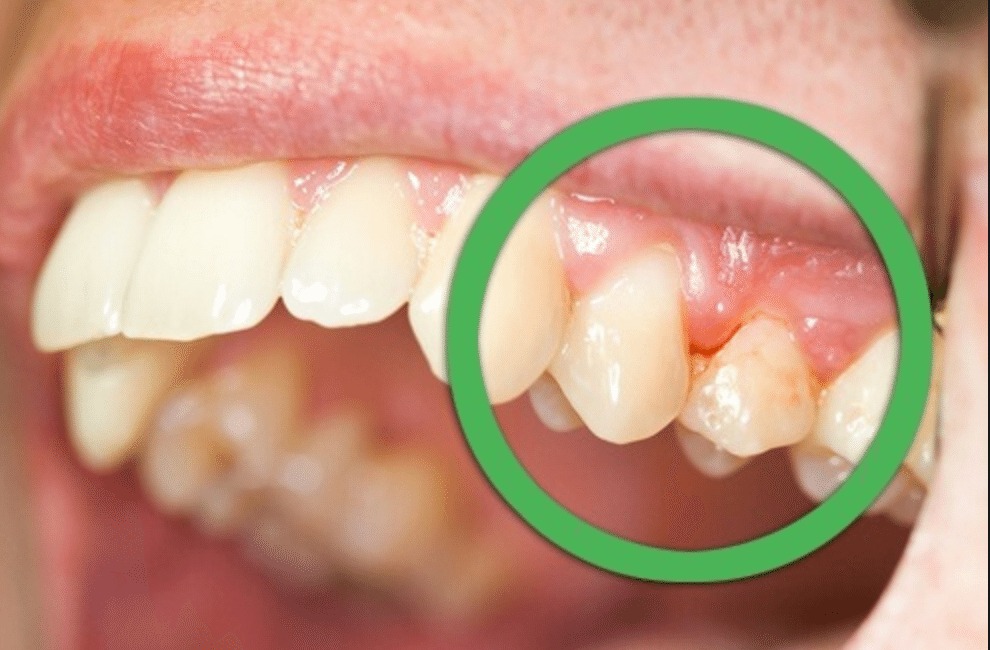

A gengivite crônica é a inflamação da gengiva que, se não tratada, pode evoluir. Ela acontece pelo acúmulo de placa bacteriana. Isso causa vermelhidão, inchaço e até sangramento ao escovar os dentes. Ignorar pode levar a problemas mais sérios, como a periodontite, que afeta os ossos que sustentam os dentes.

A gengivite crônica pode parecer uma coisa pequena, mas se não for tratada, ela pode se agravar e trazer outros problemas. É aquela inflamação persistente que deixa a gengiva inchada e às vezes sangrando. O principal culpado? Acúmulo de placa bacteriana. Pois é, aquela sujeirinha que não sai com uma escovação básica. Precisamos ser mais eficientes na limpeza diária.

Se você notar que sua gengiva está sempre vermelha, sensível ou até mesmo recuando, pode ser gengivite crônica. Não ignore esses sinais! A boa notícia é que, na maioria das vezes, com os cuidados certos em casa e, claro, acompanhamento do dentista, a situação melhora muito. Ele poderá te orientar sobre os produtos e técnicas mais adequados para o seu caso.

Quando a gengiva fica inflamada por muito tempo, a gente chama de gengivite crônica. Os sintomas podem ser sutis no começo: um sangramento leve ao escovar, um inchaço discreto. Mas, com o tempo, essa inflamação pode evoluir e comprometer a estrutura que sustenta os dentes. A limpeza interdental regular é uma arma poderosa para evitar que isso aconteça, mantendo sua gengiva saudável e sua boca feliz.

Sabe quando a gengiva fica inchada, vermelha e sangra fácil? Se isso já virou rotina, é sinal de gengivite crônica. E olha, ignorar isso só piora o quadro. Muita gente acha que é normal, mas não é. Se você não cuidar, a inflamação pode avançar e virar algo mais sério, como periodontite. Essa é a fase em que o osso que segura seus dentes começa a ser afetado. Ninguém quer chegar nesse ponto, né?

A gengivite crônica se caracteriza por uma inflamação persistente na gengiva, que fica vermelha, inchada e pode até sangrar com facilidade. Muitas vezes, a causa é o acúmulo de placa bacteriana que não foi removida corretamente com a escovação e o fio dental. Quando ela se torna crônica, os cuidados caseiros podem não ser suficientes para reverter o quadro, e a ajuda profissional se torna indispensável.